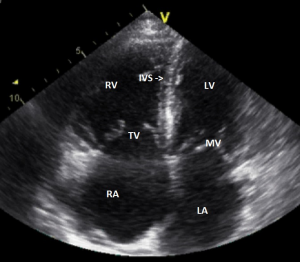

Video 1 / Figuur 1

Let op de nog redelijke linkerventrikelfunctie en de duidelijk gedilateerde boezems.

De rechter ventrikel is gedilateerd en eveneens afgenomen in functie.

Figuur 1: behorende bij video 1. Transthoracale echocardiografie. Apicale 4-kameropname. RA= rechteratrium. RV= rechterventrikel. IVS= interventriculair septum. LA=linkeratrium. LV=linkerventrikel. TV= tricuspidalisklep. MV=mitralisklep